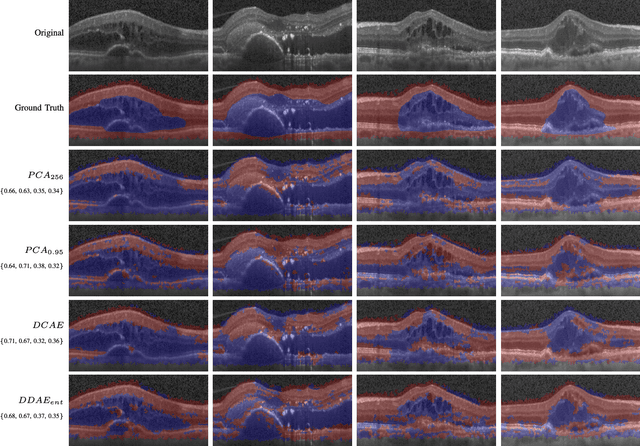

Abstract:The identification and quantification of markers in medical images is critical for diagnosis, prognosis, and disease management. Supervised machine learning enables the detection and exploitation of findings that are known a priori after annotation of training examples by experts. However, supervision does not scale well, due to the amount of necessary training examples, and the limitation of the marker vocabulary to known entities. In this proof-of-concept study, we propose unsupervised identification of anomalies as candidates for markers in retinal Optical Coherence Tomography (OCT) imaging data without a constraint to a priori definitions. We identify and categorize marker candidates occurring frequently in the data, and demonstrate that these markers show predictive value in the task of detecting disease. A careful qualitative analysis of the identified data driven markers reveals how their quantifiable occurrence aligns with our current understanding of disease course, in early- and late age-related macular degeneration (AMD) patients. A multi-scale deep denoising autoencoder is trained on healthy images, and a one-class support vector machine identifies anomalies in new data. Clustering in the anomalies identifies stable categories. Using these markers to classify healthy-, early AMD- and late AMD cases yields an accuracy of 81.40%. In a second binary classification experiment on a publicly available data set (healthy vs. intermediate AMD) the model achieves an area under the ROC curve of 0.944.

Abstract:The identification and quantification of markers in medical images is critical for diagnosis, prognosis and management of patients in clinical practice. Supervised- or weakly supervised training enables the detection of findings that are known a priori. It does not scale well, and a priori definition limits the vocabulary of markers to known entities reducing the accuracy of diagnosis and prognosis. Here, we propose the identification of anomalies in large-scale medical imaging data using healthy examples as a reference. We detect and categorize candidates for anomaly findings untypical for the observed data. A deep convolutional autoencoder is trained on healthy retinal images. The learned model generates a new feature representation, and the distribution of healthy retinal patches is estimated by a one-class support vector machine. Results demonstrate that we can identify pathologic regions in images without using expert annotations. A subsequent clustering categorizes findings into clinically meaningful classes. In addition the learned features outperform standard embedding approaches in a classification task.